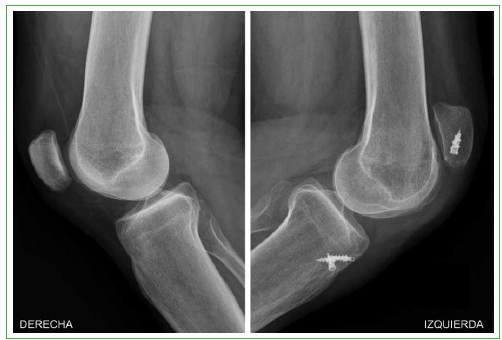

Figura 2.

Radiografías de rodilla, de perfil, comparativas. Se observa el ascenso de la rótula en la rodilla izquierda en comparación con la altura de la rótula en la rodilla derecha (índice de Insall-Salvati de 2 y 1,2, respectivamente).